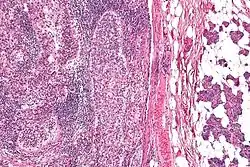

![]() صورة مجهرية للسرطانة الزهمية (يسار الصورة). انبثاث في الغدة النكافية (يمين الصورة). صبغة الهيماتوكسيلين واليوزين (H&E stain). صورة مجهرية للسرطانة الزهمية (يسار الصورة). انبثاث في الغدة النكافية (يمين الصورة). | |